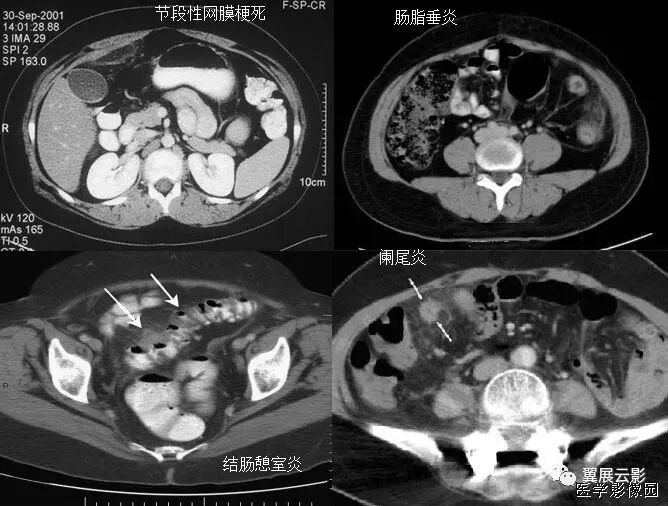

3、不成比例脂肪绞缠征

不成比例脂肪绞缠主要指的是增厚肠壁和周围脂肪在数量方面比例的严重失衡。在少数急性胃肠道疾病中,以肠壁相邻的肠系膜为中心而不是以肠壁为中心,因此肠壁周围脂肪增厚明显高于肠壁厚度。和这一征像相关的疾病主要包括4类:憩室炎、肠脂垂炎、网膜梗死和阑尾炎。胃肠道的大多数炎性疾病包括感染性的、非感染性的和局部缺血性的病变,都是以肠道为中心。这些疾病的肠壁增厚程度往往超过相邻脂肪条索的厚度。但是对于少数以肠壁临近系膜为中心的疾病,脂肪增生明显超过肠壁的厚度。

左上图:右侧腹横肌深面、胆囊内前方梭形囊性病变,有壁但不均匀,略有强化。与腹横肌成锐角,腹横肌肥厚。周围脂肪模糊,有索条点状影。

右上图:邻近降结肠远端系膜壁旁可见一卵圆形类似脂肪密度的病变,周边可见火焰样炎性改变,邻近肠壁有轻微增厚,无明显脓肿及肠梗阻征象。

左下图:肠壁增厚,结肠袋襞显影不良,以及结肠周围脂肪束条状改变。

右下图:CT显示壁明显增强的管状结构(箭头),右中腹的脂肪系膜反应。